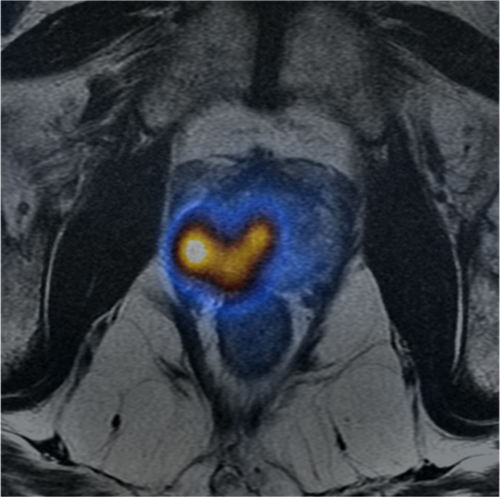

3D volumetric imaging with an optimized adiabatic fat suppression, combined with ARC or ASSET, provides high spatial and temporal resolution to capture contrast uptake patterns. The FSPGR Ax Dynamic image shows lesion characteristics generated using AW VS7's positive enhancement map. The T2 PROPELLER image demonstrates small FOV and motion-correction through the prostate.OrthoWorks